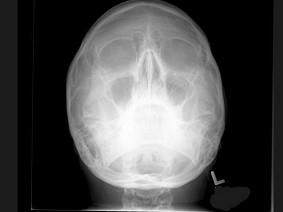

问题 25岁女性,车祸伤及面部,X线及CT检查如图所示,下列哪些描述或诊断正确 ( )

选项 A、考虑为左侧眶底骨折 B、左侧上颌窦积液 C、CT发现左侧眶底骨质断裂 D、左侧上颌窦内见气-液面 E、X线示左侧眶底较正常变低

答案 ABCDE